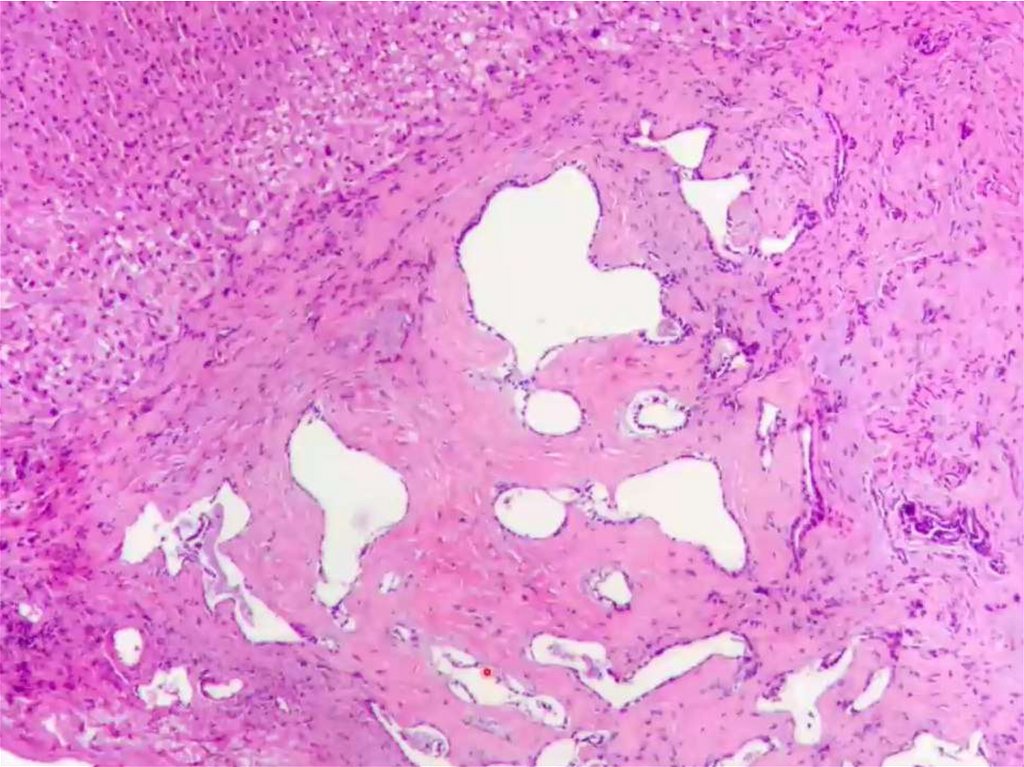

Cholangicarcinoma